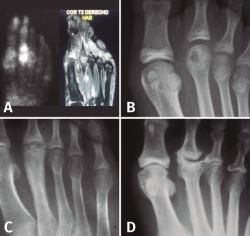

Figura 3. Fases evolutivas de la necrosis. A: fase inicial; B: fase de reparación; C: fase de repercusión articular; D: fase artrósica.

Como en todas las necrosis óseas, la radiología es característica y se corresponde con la fase evolutiva de la necrosis (Figura 3):

- Fase inicial en la que se produce la isquemia con la consiguiente muerte celular. En esta primera fase la radiología es negativa y el diagnóstico se establece con la ayuda de la gammagrafía y la resonancia magnética nuclear (RMN).

- Fase de reparación en la que existe una revascularización alrededor de la zona necrótica: vemos en la cabeza una zona más densa, que corresponde al hueso necrosado, y una zona radiolúcida alrededor de ella, que corresponde a la hiperemia.

- Fase de repercusión articular: el cartílago articular se hunde al fallarle el soporte mecánico del hueso subcondral.

- Fase artrósica en la que se ha producido la desestructuración de la articulación con pérdida del espacio articular y reacción osteofítica, tanto en la cabeza del metatarsiano como en la base de la falange.